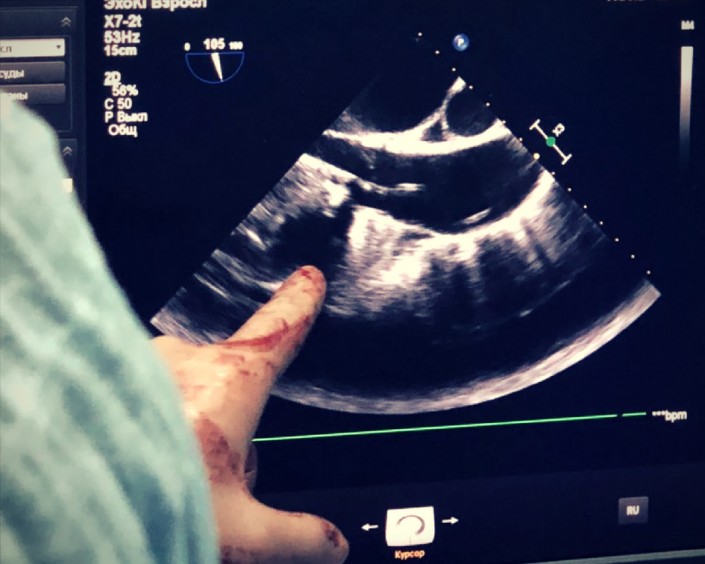

Далее производим несколько снимков, с помощью которых мы смотрим, куда и как движется катетер с клапаном.

Снова делаем снимки и через рентген проверяем, как действует наша установка.